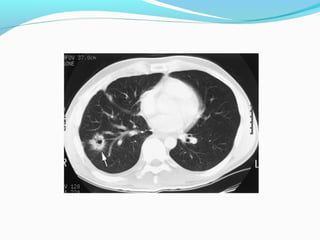

STAGE ??